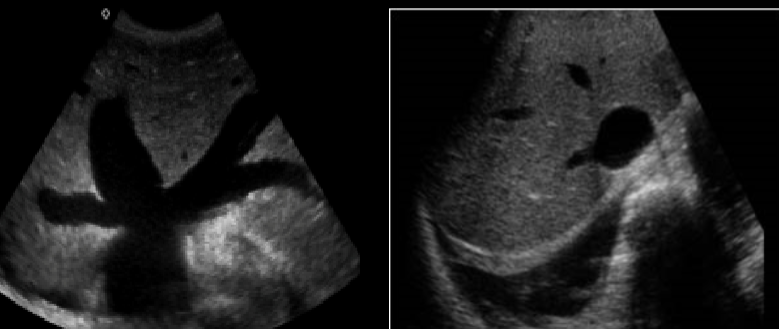

collaterals/varices/cavernous transformation

PV thrombosis